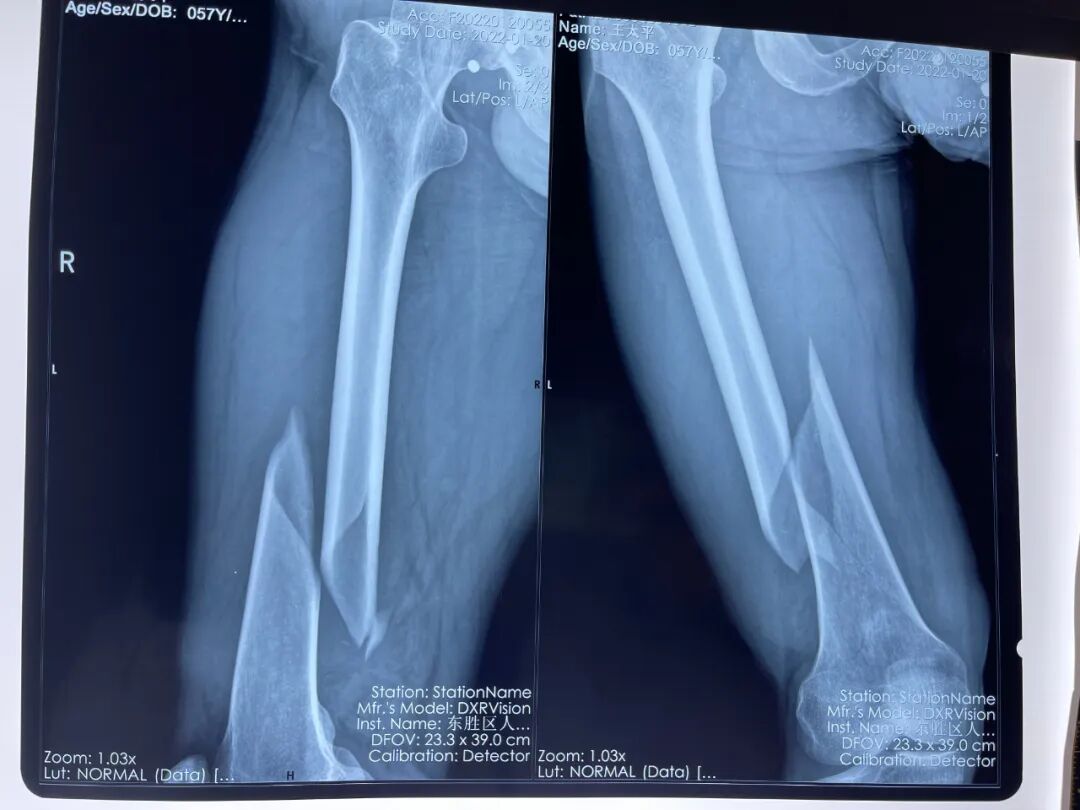

57歲的王先生,在趕牛時不慎被奔跑的牛拉倒,強大的沖擊力使得他的右大腿嚴(yán)重扭曲變形,家人立即將他送往我院治療。劉智副主任醫(yī)師接診經(jīng)過系統(tǒng)的檢查發(fā)現(xiàn),王先生的右大腿發(fā)生了骨折,股骨遠(yuǎn)端錯位非常明顯。其右腿仍然腫脹、疼痛感非常厲害。

圖片

術(shù)前

股骨是人體長度最長、硬度最大、承擔(dān)負(fù)荷最多的長管狀骨,臨床上的股骨骨折多是由巨大暴力引起的,但像這個病例粉碎骨折、移位顯著。